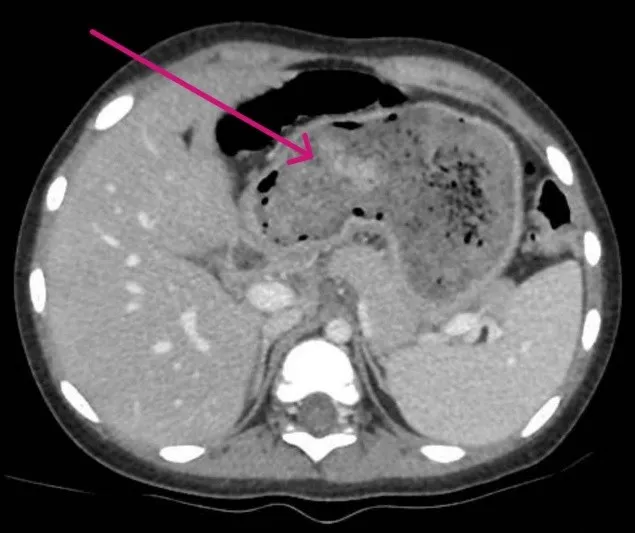

Qua thăm khám và chụp CT-scan, các bác sĩ phát hiện một búi tóc chiếm gần như toàn bộ dạ dày và kéo dài qua tá tràng xuống ruột non. Đây là biểu hiện điển hình của trichobezoar (búi tóc trong dạ dày) tiến triển thành hội chứng Rapunzel. Em A. được chỉ định phẫu thuật mở dạ dày để lấy búi tóc ra ngoài.

hình ảnh scan.jpg

Hình ảnh scan búi tóc